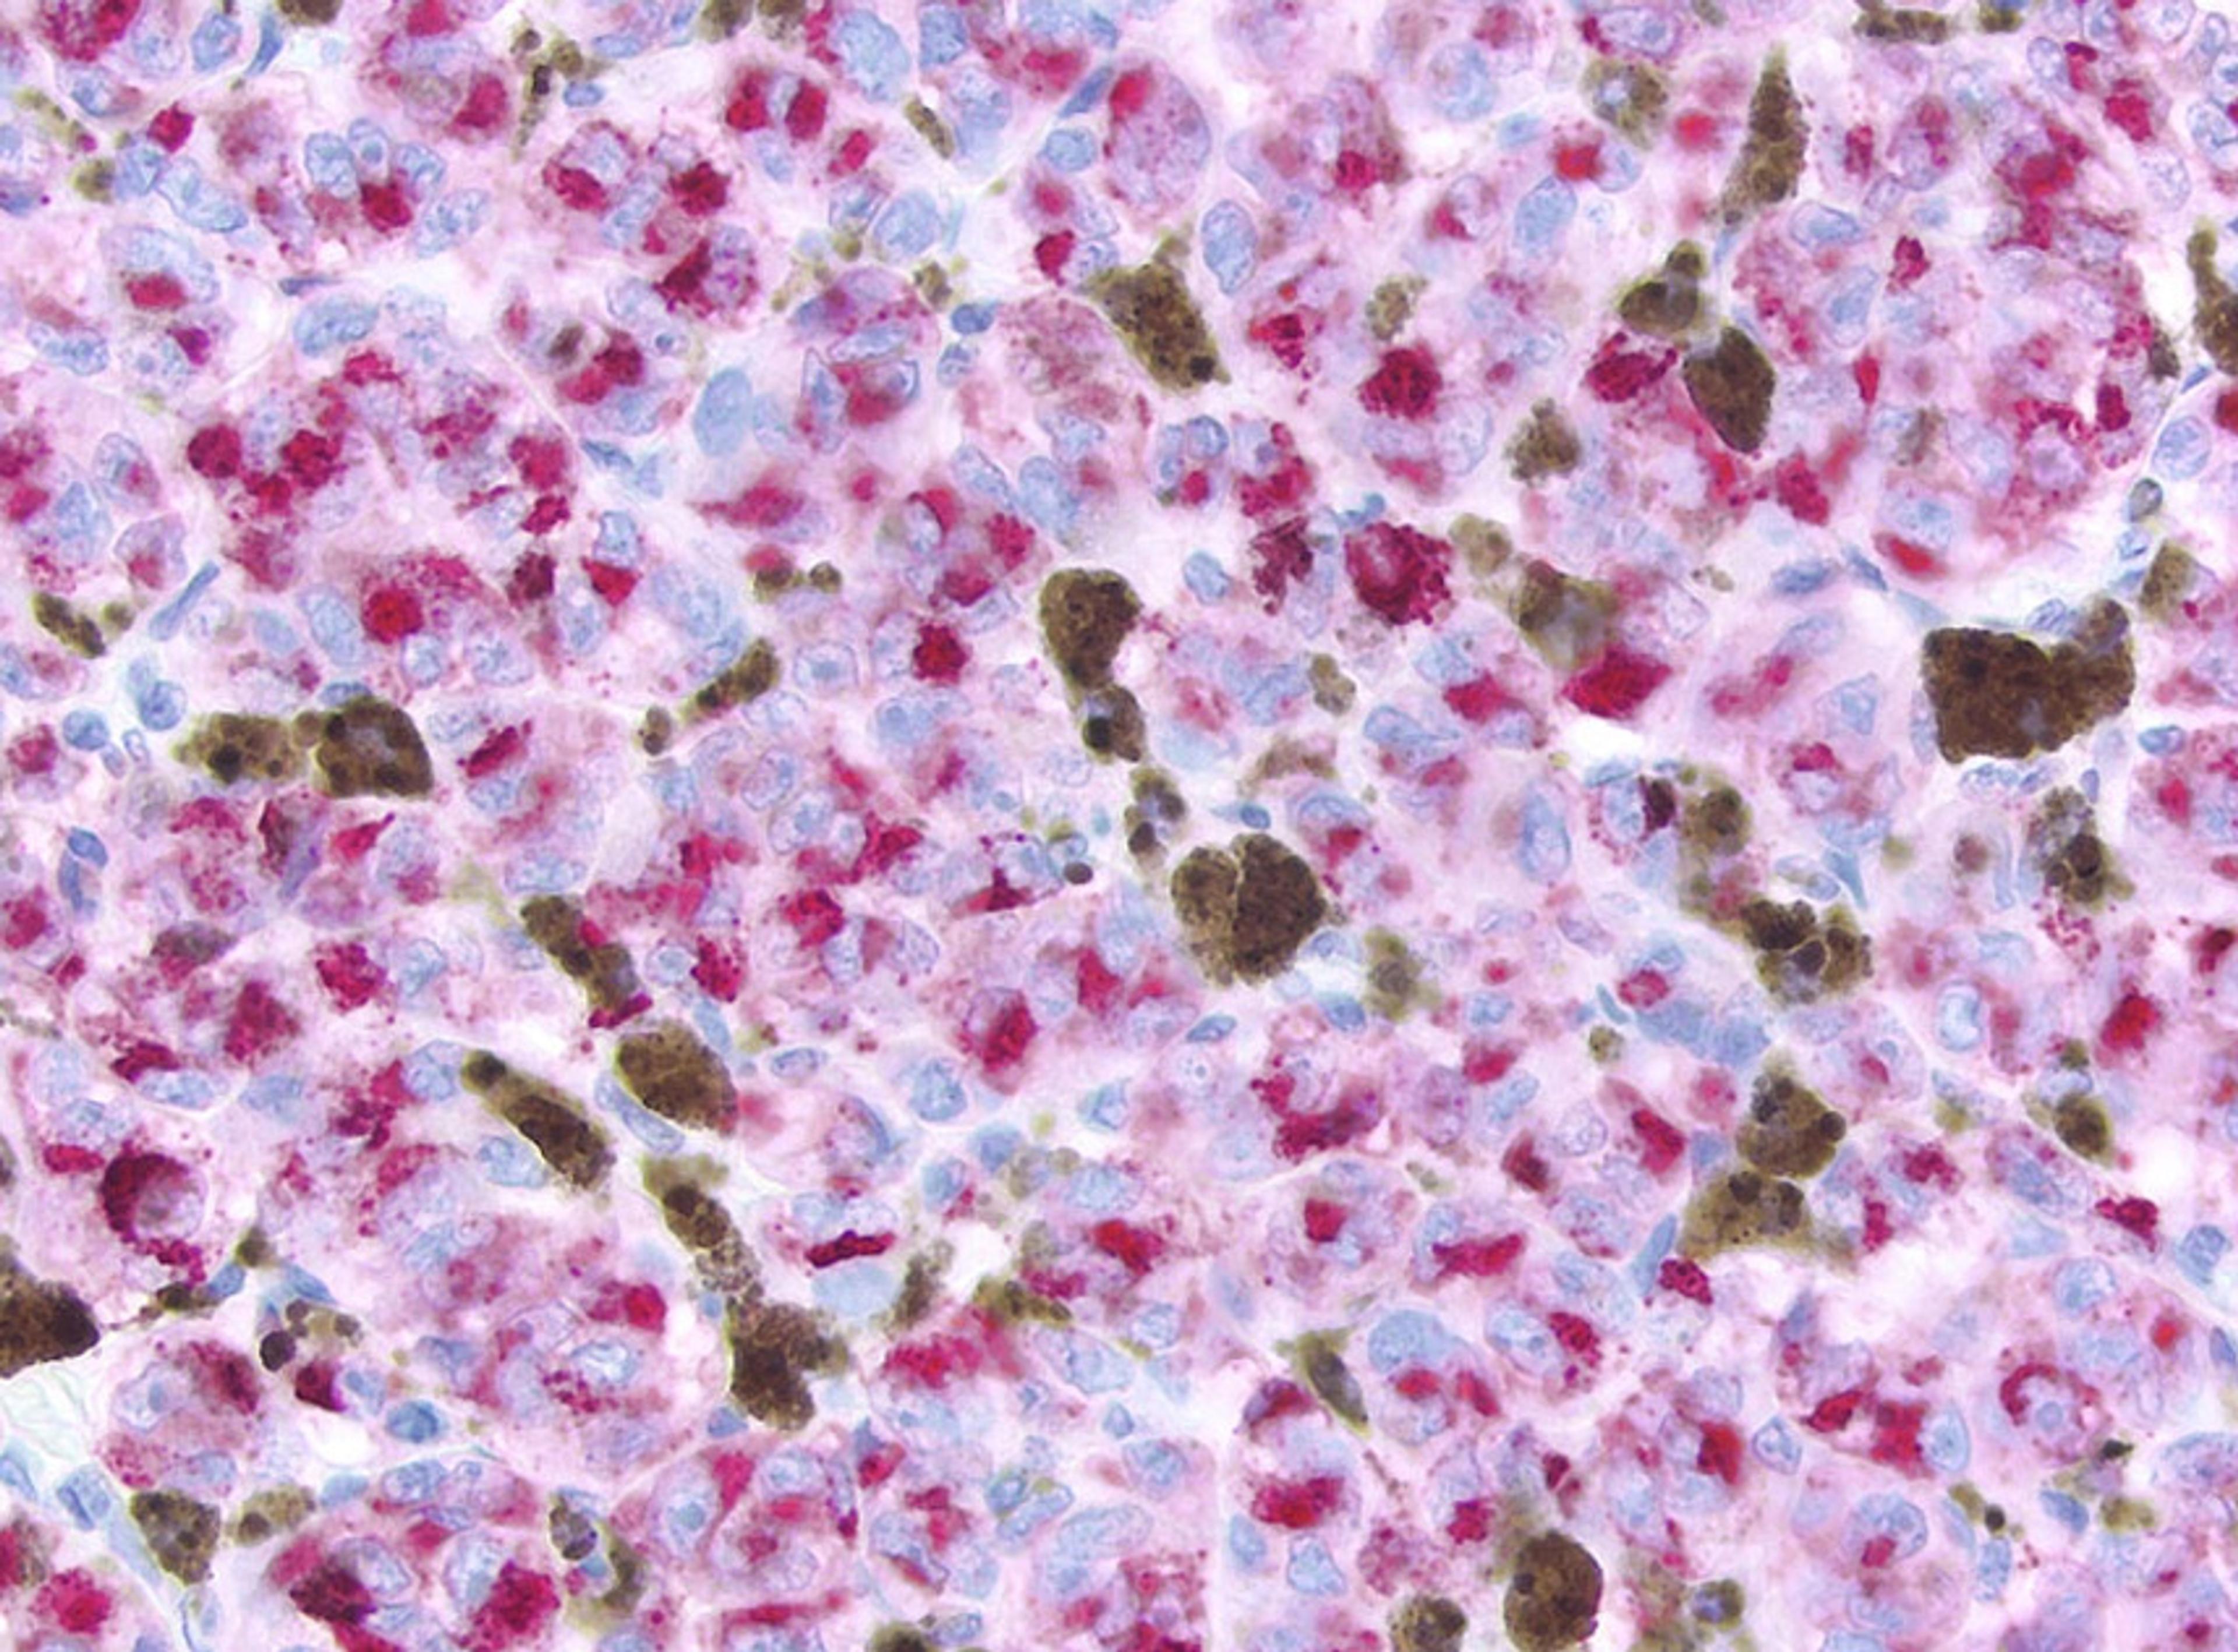

RNAscope and IHC analysis

We are interested in applying HALO AI in RNAscope and IHC analysis. Thanks to Yongtian ZHAO to give us wonderful training and support. We are improving and confident to apply it in the RNAscope assay development and scoring.

RNAscope image analysis using HALO and HALO AI

In this application note, discover how the ISH module and FISH module available with the HALO® image analysis platform can be employed with HALO AI™ to quantitatively assess chromogenic and fluorescence RNAscope assays, respectively.